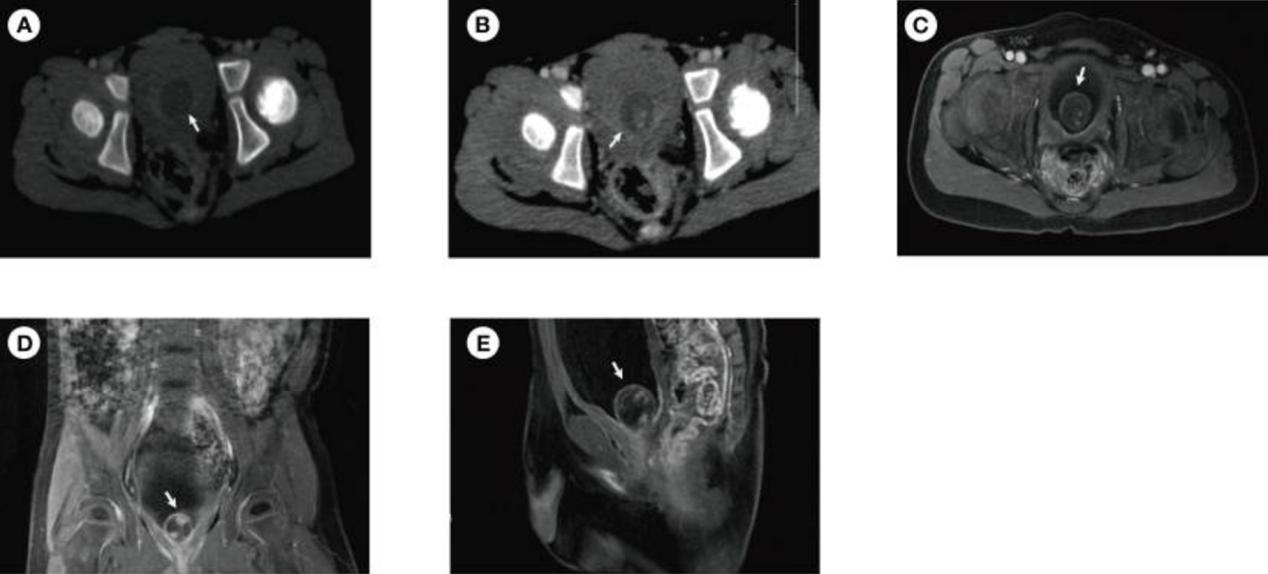

一名3岁男孩因尿频1个月入院,体格检查未见明显异常。外院尿液分析显示,尿液白细胞计数升高,为17.9/ul。超声显示膀胱肿物。CT平扫显示圆形、低密度、边缘良好的膀胱病变(1.9×1.8cm)(图1A)。CT增强扫描显示病变包膜中度圆形增强,病变实质中有小片状增强的高密度阴影(图1B)。MRI扫描显示一个囊性病变(1.9×1.9cm),病变包膜呈环形低信号,膀胱三角区有一个片状增强的病变实质(图1C–E)。

图1 术前患者的CT和MRI(A) CT平扫显示圆形、低密度、边缘良好的膀胱病变(1.9×1.8cm)。(B) CT增强扫描显示病变包膜中度圆形增强,病变实质内有小片状增强的高密度影。MRI显示一个囊性病变(1.9×1.9 cm),病变包膜呈环形低信号,横向(C)、冠状(D)和矢状面(E)有一个小片状增强的病变实质。图像中的白色箭头表示病变

膀胱异位海绵体的临床表现是尿频。然而这是非特异性的,因为大多数儿童膀胱肿瘤会引起尿频或血尿。需要进行影像学检查以明确诊断。与成人相比,评估儿童膀胱病变的一线成像工具是超声检查,如果肿物的起源不清楚或怀疑远处扩散,则随后进行横断面成像检查,如计算机断层扫描或磁共振成像。需要注意的是,MRI优于CT,因为在儿科人群中有辐射(该患者同时进行CT和MRI检查是不规范的)。在本例中,超声显示可能有膀胱肿物。MRI显示囊性病变,病变包膜呈环形低信号,膀胱三角区有一小块增强的病变实质,这表明膀胱肿瘤(倾向于良性)。